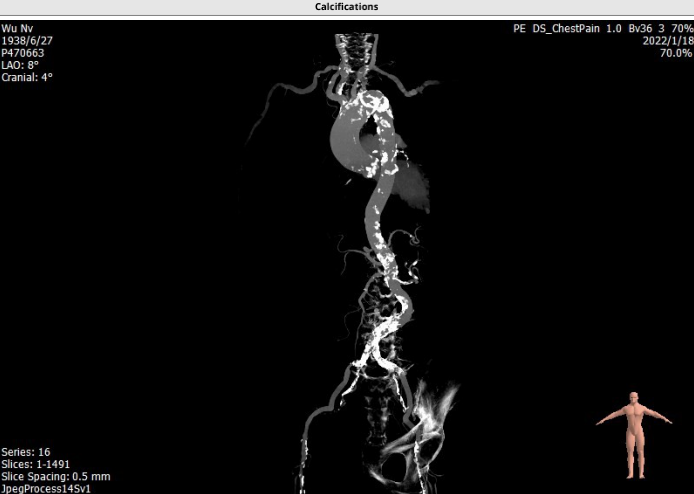

主动脉CTA:

主入路CTA:

吴伟、李荣教授团队术前总结了该病例特点:此例患者为三叶瓣重度主动脉瓣狭窄病人,瓣环72.8mm,LVOT24.0 mm,瓦式窦均径30mm,STJ 28.3mm,升主动脉41.2mm,左冠高度8.3mm,右冠高度14.4mm,下肢入路右侧血管最小径4.8mm,左侧最小径3.8mm,通过入路超声造影,显示右侧入路血管极其狭窄且重度钙化,特别是主动脉弓部钙化较重,但主动脉根部解剖形态较好,瓣叶钙化较重,考虑到球囊预扩后瓣叶可推开,由于左冠开口较低,在选择球囊型号和输送系统型号上是本次手术的关键点。

经过手术团队反复评估和研讨后,该病例为极高难度患者,主要有以下几点,一:血管入路条件极差,血管最小径在5mm以下,术中可能存在血管撕裂风险。二:外周血管存在严重钙化,为股动脉穿刺带来极大挑战,可能需要行外科切开术;三:左冠开口较低,可能存在冠脉堵塞风险;四:横位心,且腹主动脉扭曲血管内钙化较重,输送系统过弓困难。